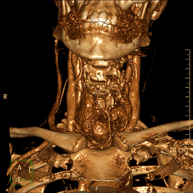

Prueba radiológica que consiste en obtener imágenes del hueso peñasco del temporal (oído interno, medio y externo) de alta definición anatómica mediante el empleo de un equipo de TC (Tomografía Computarizada). Indicaciones: pérdida de audición súbita o crónica, cuadros vertiginosos, mareo, malformaciones congénitas. - Angio – TC Troncos Supraaórticos

Prueba radiológica que consiste en obtener imágenes de las arterias carótidas del cuello de alta definición anatómica mediante el empleo de un equipo de TC (Tomografía Computarizada) y la inyección de contraste intravenoso. Posteriormente, las imágenes son reconstruidas en tres dimensiones (3D). Indicaciones: accidente vascular cerebral agudo, accidente vascular transitorio, soplo carotídeo. - TC Columna cervical